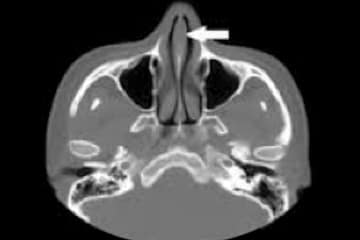

La tomografía computarizada de nariz y senos paranasales utiliza un equipo especial de rayos X para evaluar las cavidades en los senos paranasales.

Facilita la creación de imágenes 3D avanzadas para exámenes de oído, nariz, garganta, dentomaxilofacial y craneal.